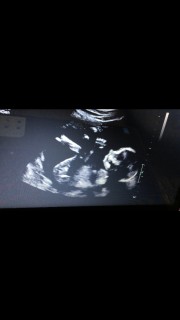

最近激しく胎動を感じます! 女の子かもと先生に言われました♪ 写真は指しゃぶりしてます♪♪♪

正面向きで顔に沿わせた右手が見えます。

頭を掻いているのかな?